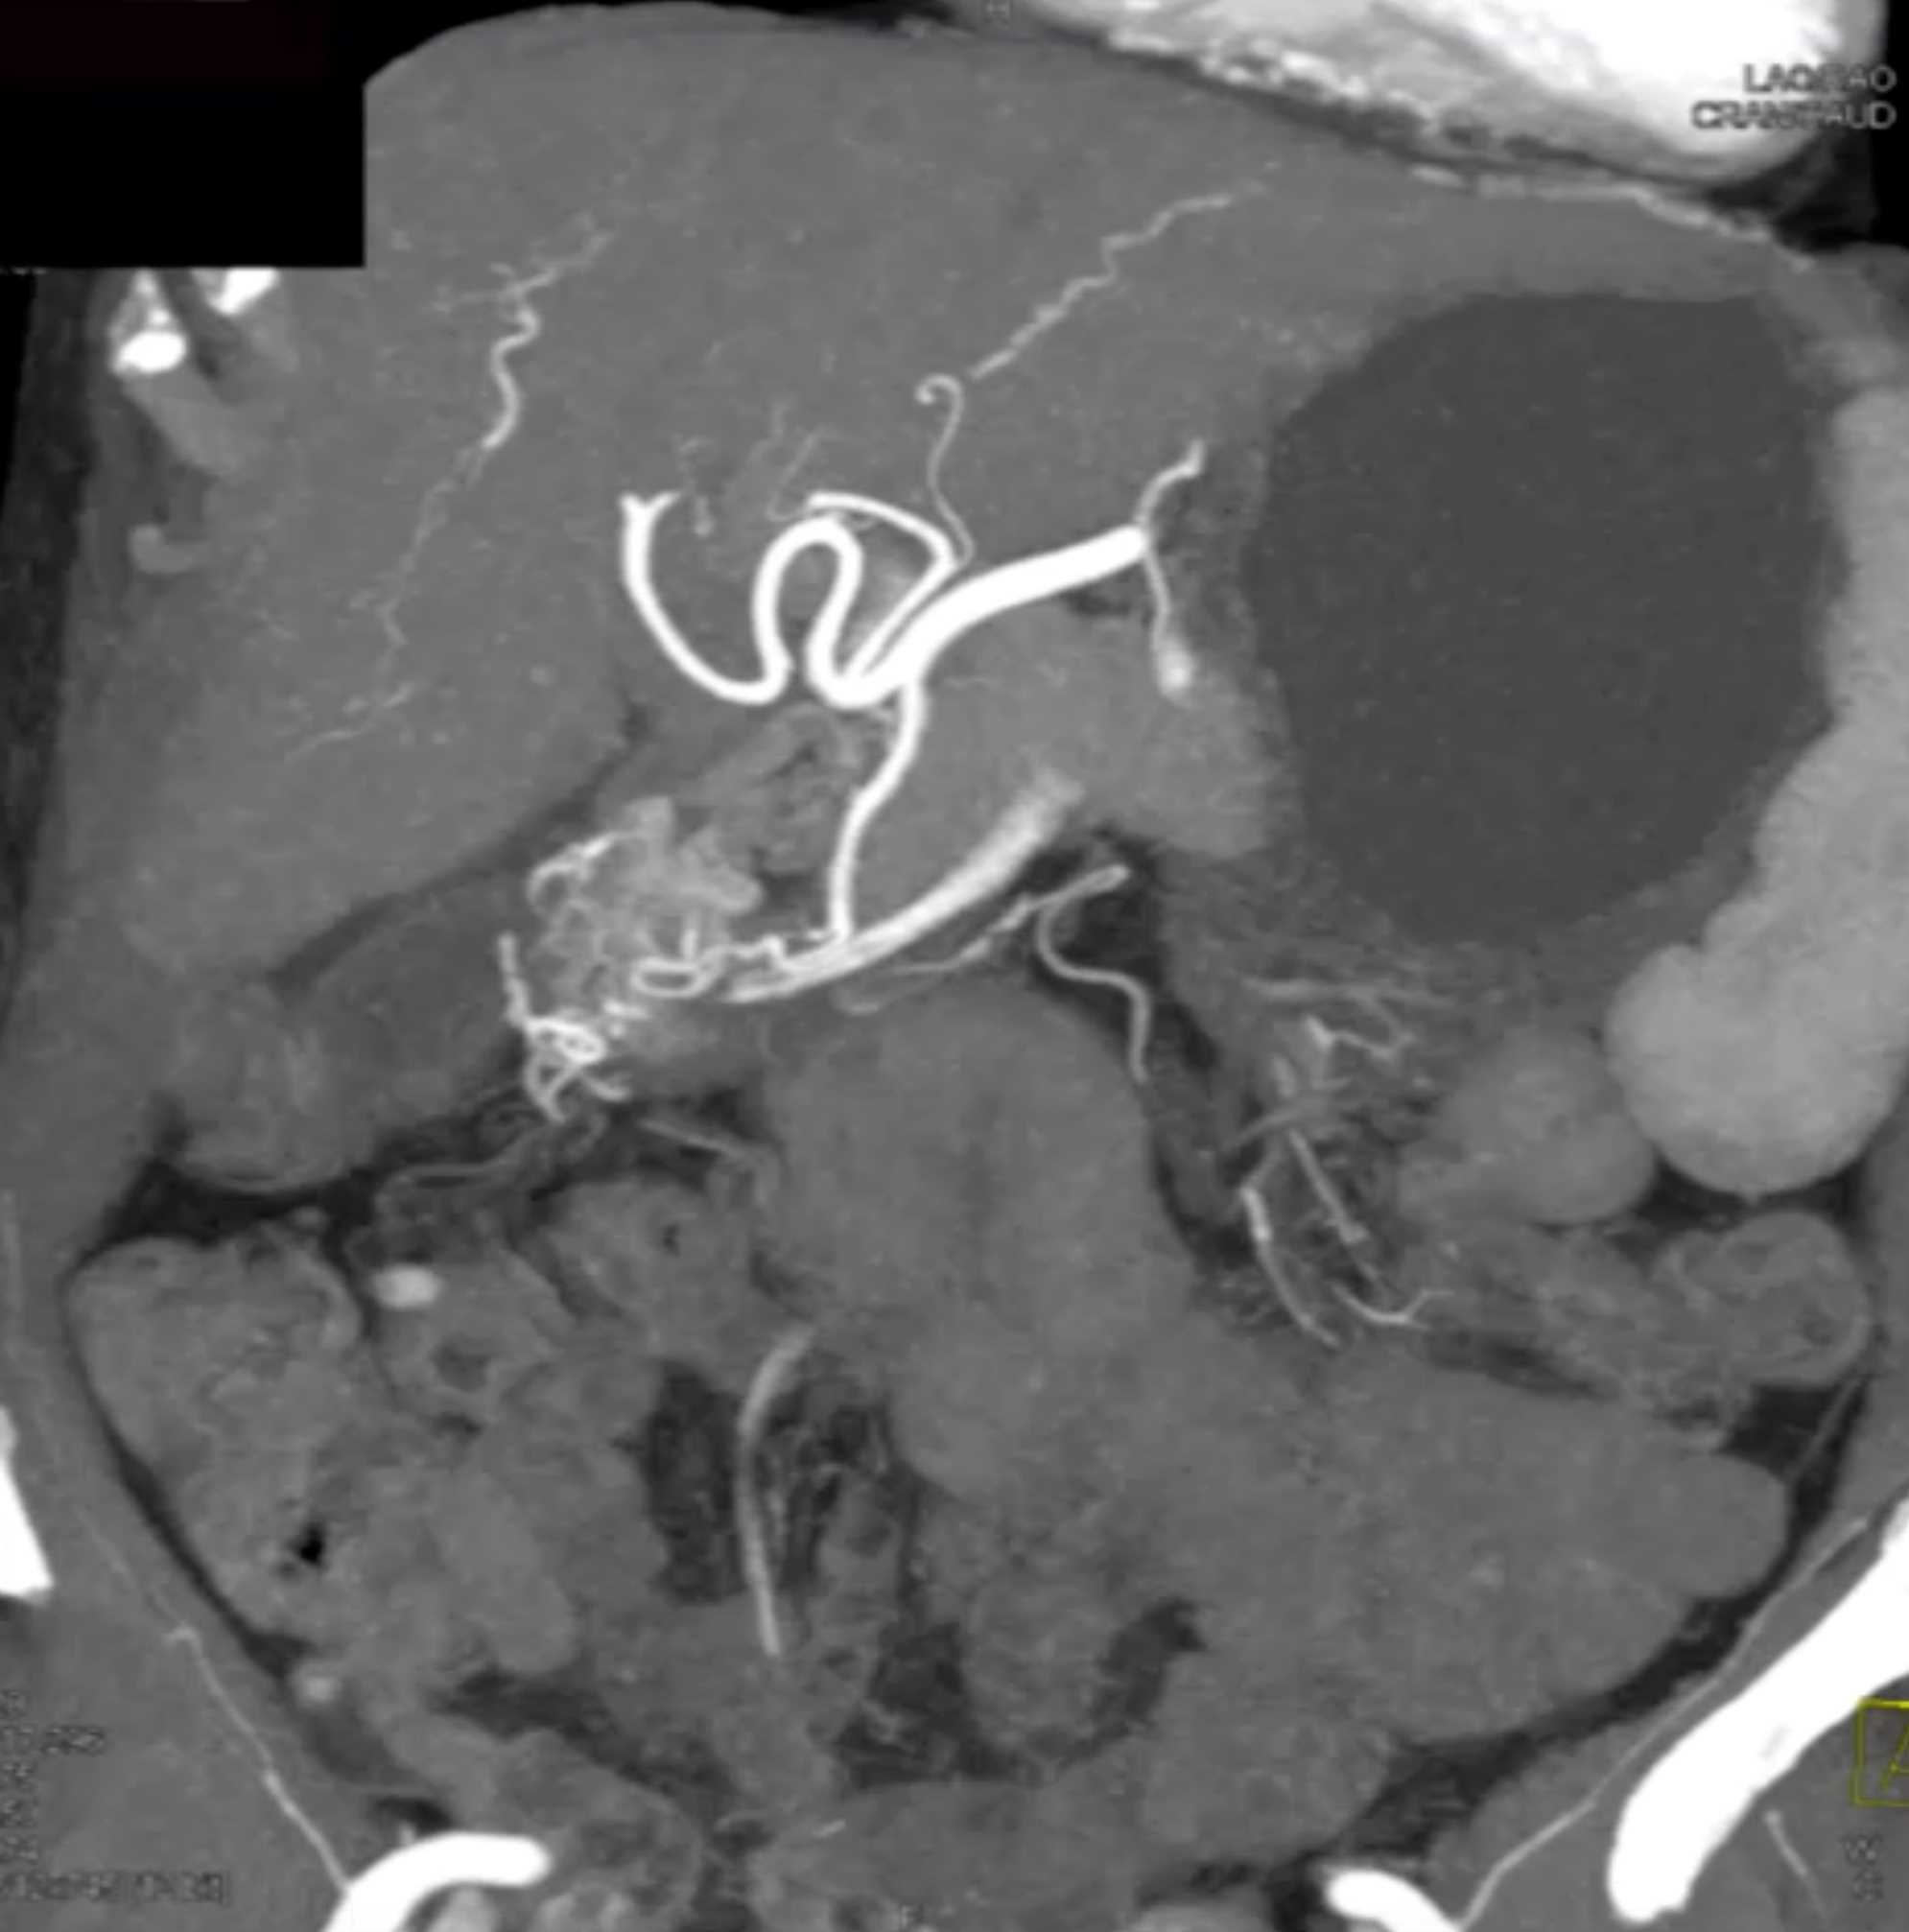

Watermelon Stomach (Gastric Antral Vascular Ectasis)